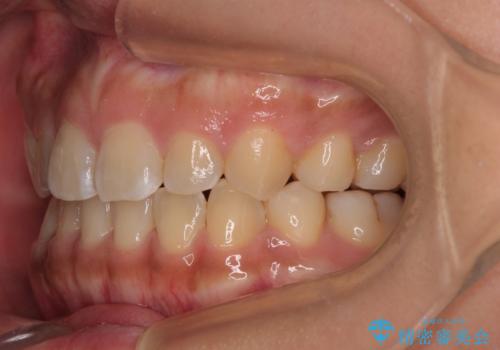

デコボコと捻れて前に飛び出した歯列 抜歯矯正でスッキリした口元に

- 前歯のデコボコと口元の突出感を気にして来院された患者様です。

非抜歯矯正ではデコボコを解消することでより口元が突出してしまうため、上下左右の小臼歯4本の抜歯を行い、ワイヤー装置による矯正治療を行うこととしました。

上顎小臼歯の歯根が左右ともに大きく曲がっており、スペースクローズに時間がかかってしまいました。